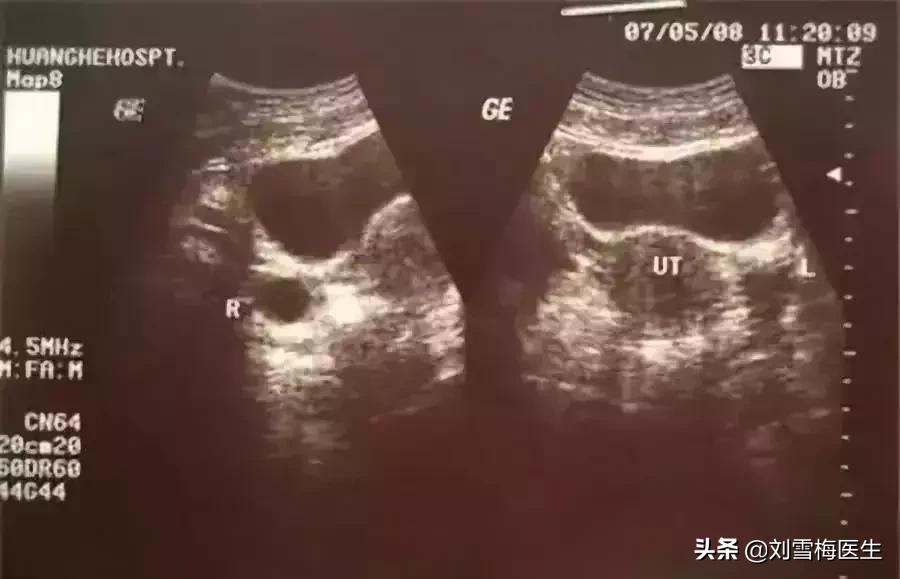

测量基础体温来监测太麻烦也影响睡眠,排卵试纸又不能准确测到排卵时卵泡的大小,采用B超监测排卵是最好的,这种方法可以准确的知道排卵的时间、排卵时卵泡的大小、排卵时内膜的厚度和形态。

一般在月经周期第10天左右开始监测,观察卵泡直径的变化,在排卵前4天的卵泡直径平均每天约增3mm,在排卵前卵泡成熟约18-25mm,排卵后卵泡消失,连续监测可见在排卵前卵泡不断长大,当最大的卵泡消失时,提示发生排卵。

第2次B超:在月经第10天左右,可以看到1-2个优势卵泡,并能计算卵泡生长的速度。

第3次B超:月经第13天左右,恰恰在排卵前,这时B超会出现卵泡周围透声环,有经验的医生会告诉你,卵泡应该在24小时内排卵。

第4次B超:刚刚排卵后第14天左右,卵泡已经消失或显著缩小5mm以上,子宫直肠隐窝内可见液性暗区4-6mm,甚至更多。